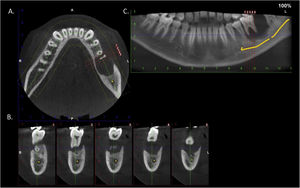

An 11-year-old boy was consulted because of local pain and paresthesia of the left lower lip during an unknown amount of time. He had a history of grade II ependymoma, which was appropriately treated with surgery and radiotherapy and controlled routinely. He had no systemic symptoms, known allergies or medical history of any other illness. Extra-oral examination revealed no anomalies. Intraorally, a mass involving both the buccal and lingual gingiva between the lower left second molar and lower left first premolar was observed. An extensive verrucous white patch was covering the buccal side of the mass, while cystic-like white nodules with superficial blood vessels were also present on both the lingual and buccal sides of the tumor (Fig. 1). The teeth involved in the mass were mobile. Cone-beam computed tomography revealed a well-defined large radiolucency involving the whole thickness of the posterior left mandible perforating the buccal bone plate (Fig. 2). An incisional biopsy was taken which showed a tumoral mass composed of multiple branching keratin-filled crypts sheets lined by epidermoid epithelial cells. The endophytic epithelial growth pattern burrowed deep inside into the alveolar bone, forming a complex network of connected canaliculi, resembling rabbit burrows. The epithelial cells were well differentiated, and no atypia, mitosis, perineural nor lymphovascular invasion was observed. A chronic inflammatory infiltrates consisting mainly of lymphocytes with local areas of neutrophil accumulation was observed in some areas of the stroma (Fig. 3). The lesion was diagnosed as a carcinoma cuniculatum of the oral cavity. Differential diagnosis with a solid variant of an odontogenic keratocyst was done due to its histopathological similarity. The CT scan examination revealed no lymph node involvement and no metastasis, and the patient was referred for surgical treatment. The patient was controlled with regularity and no recurrences have been observed after a 5-years-follow up period.